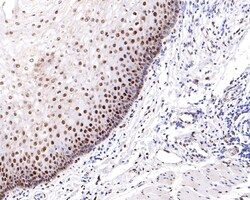

Invitrogen™ Phospho-ATF2 (Thr71) Recombinant Rabbit Monoclonal Antibody (SC05-90)

The transcription factor ATF-2 (also called CRE-BP1) binds to both AP-1 and CRE DNA response elements and is a member of the ATF/CREB family of leucine zipper proteins. ATF-2 interacts with a variety of viral oncoproteins and cellular tumor suppressors and is a target of the SAPK/JNK and p38 MAP kinase signaling pathways. Various forms of cellular stress, including genotoxic agents, inflammatory cytokines and UV irradiation, stimulate the transcriptional activity of ATF-2. Cellular stress activates ATF-2 by phosphorylation of Thr69 and Thr71. Both SAPK and p38 MAPK have been shown to phosphorylate ATF-2 at these sites in vitro and in cells transfected with ATF-2.

| Immunohistochemistry (Paraffin), Western Blot, Immunocytochemistry | |